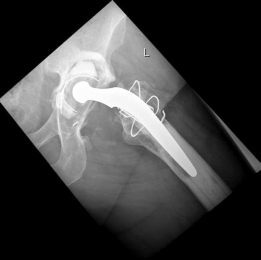

Reconstruction techniques : Acetabulum— augment buttress, morcellized bone grafting, porous tantalum shell. Femur—modular revision stem, trochanteric plate, cerclage cables (Figs. 19.20 and 19.21).

7. #### Postoperative Radiographs

(Figs. 19.20 and 19.21)